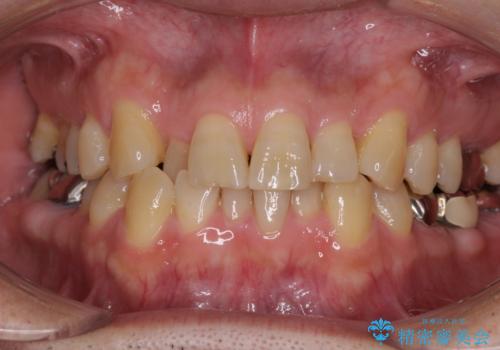

- 隙間をセラミックで閉じたら不格好で歯肉から出血 矯正治療と歯周外科で綺麗な前歯に